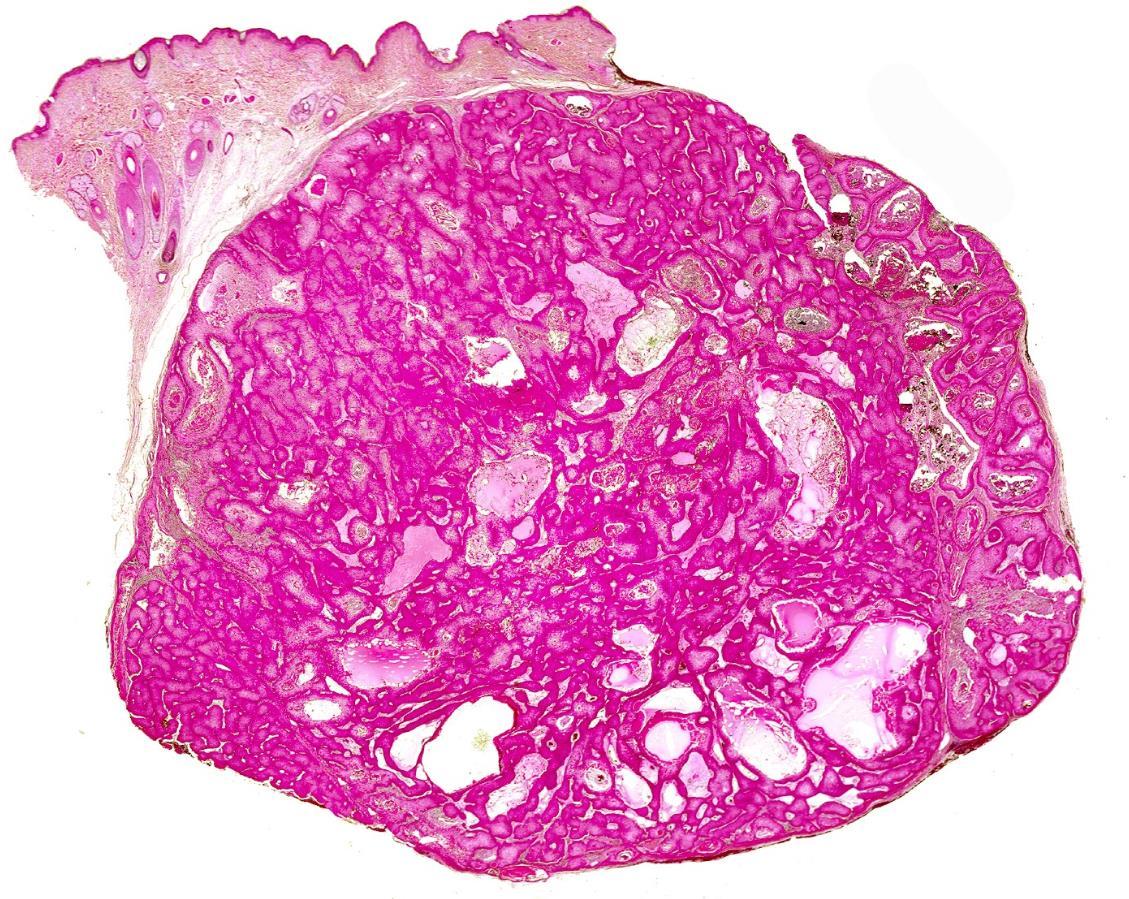

• Proliferating trichilemmal tumour

• Solid-cystic neoplasm with differentiation towards outer root sheath

• Well defined interconnected proliferation of squamoid cells